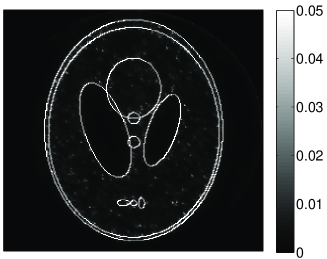

• [63] C. W. Dodge, A rapid method for the simulation of filtered X-ray spectra in diagnostic imaging systems (ProQuest, 2008).